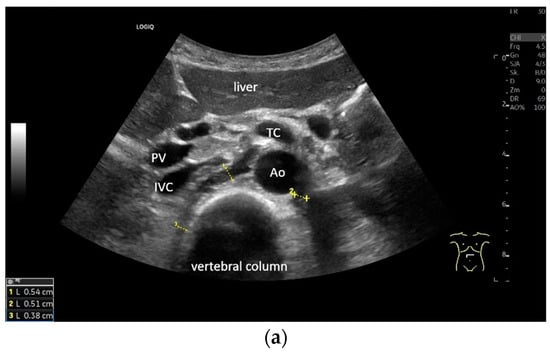

Subxiphoid: The diaphragm can be positioned directly subxiphoidally with a slightly sagittal transducer position on both sides next to the attachment to the sternum. The diaphragm limb can be demarcated to the right in the epigastrium in cross section between the aorta and the inferior vena cava. However, this is primarily of differential diagnostic importance, e.g., in relation to lymphomas, not for the actual assessment of the diaphragm (Figure 6).